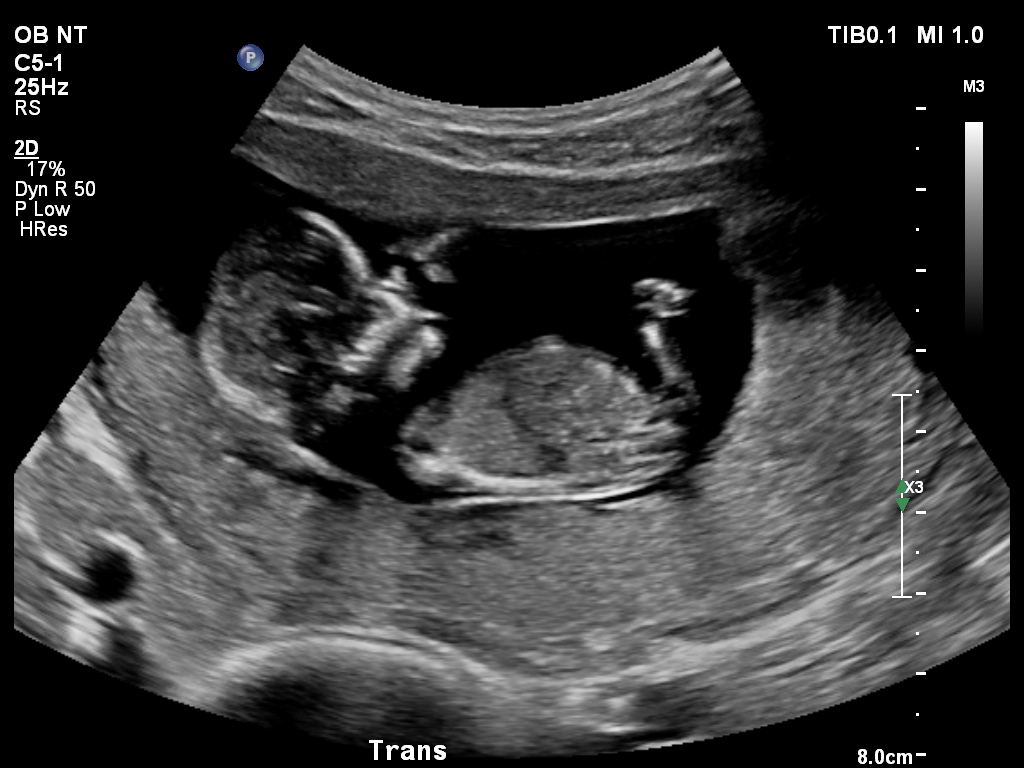

Hi there! DH and I are "technically" team green, however I am dying to know what this one is as we have a little boy at home. I automatically thought this was all boy, but have since been told that the "fork" can actually mean girl? No other nub shots to compare with, sadly.

Thoughts? Taken at 13w exactly.

**NEW PIC ADDED, better nub shot?**Attachment 26461